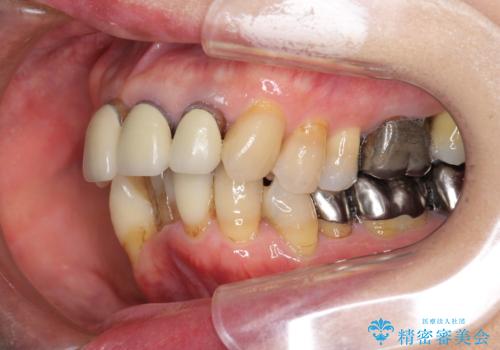

- 前歯の見た目・歯並び・銀歯の見た目の改善を求めて来院されました。

まずガタ付きの強い歯並びをマウスピース矯正インビザラインで整えたのち、セラミック治療による審美性の改善を計画します。